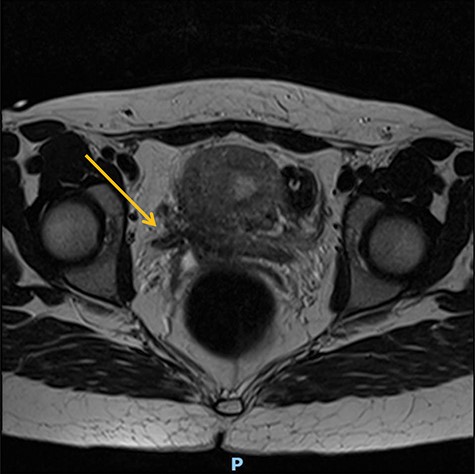

At a 1-year follow-up, the patient was complaining of flank pain, so an technetium-99m mercaptoacetyltriglycine renography (MAG3) was performed, showing good drainage but mild to moderate reflux into the reimplanted ureter. Normal bladder and sexual function were restored, and she was discharged from routine follow-up after 18 months. Following successful conception, she had a specialist obstetric review and was planned to have an elective C-section at between 37 and 38 weeks to avoid labour. Unfortunately, she had a premature vaginal delivery due to chorioamnionitis at 23 + 4 gestation complicated by sepsis with features of shock from which she and her baby made a full recovery (Figs. 1 and 2).

Preoperative MR abdomen, transverse plane. Arrow indicating obstructed right ureter